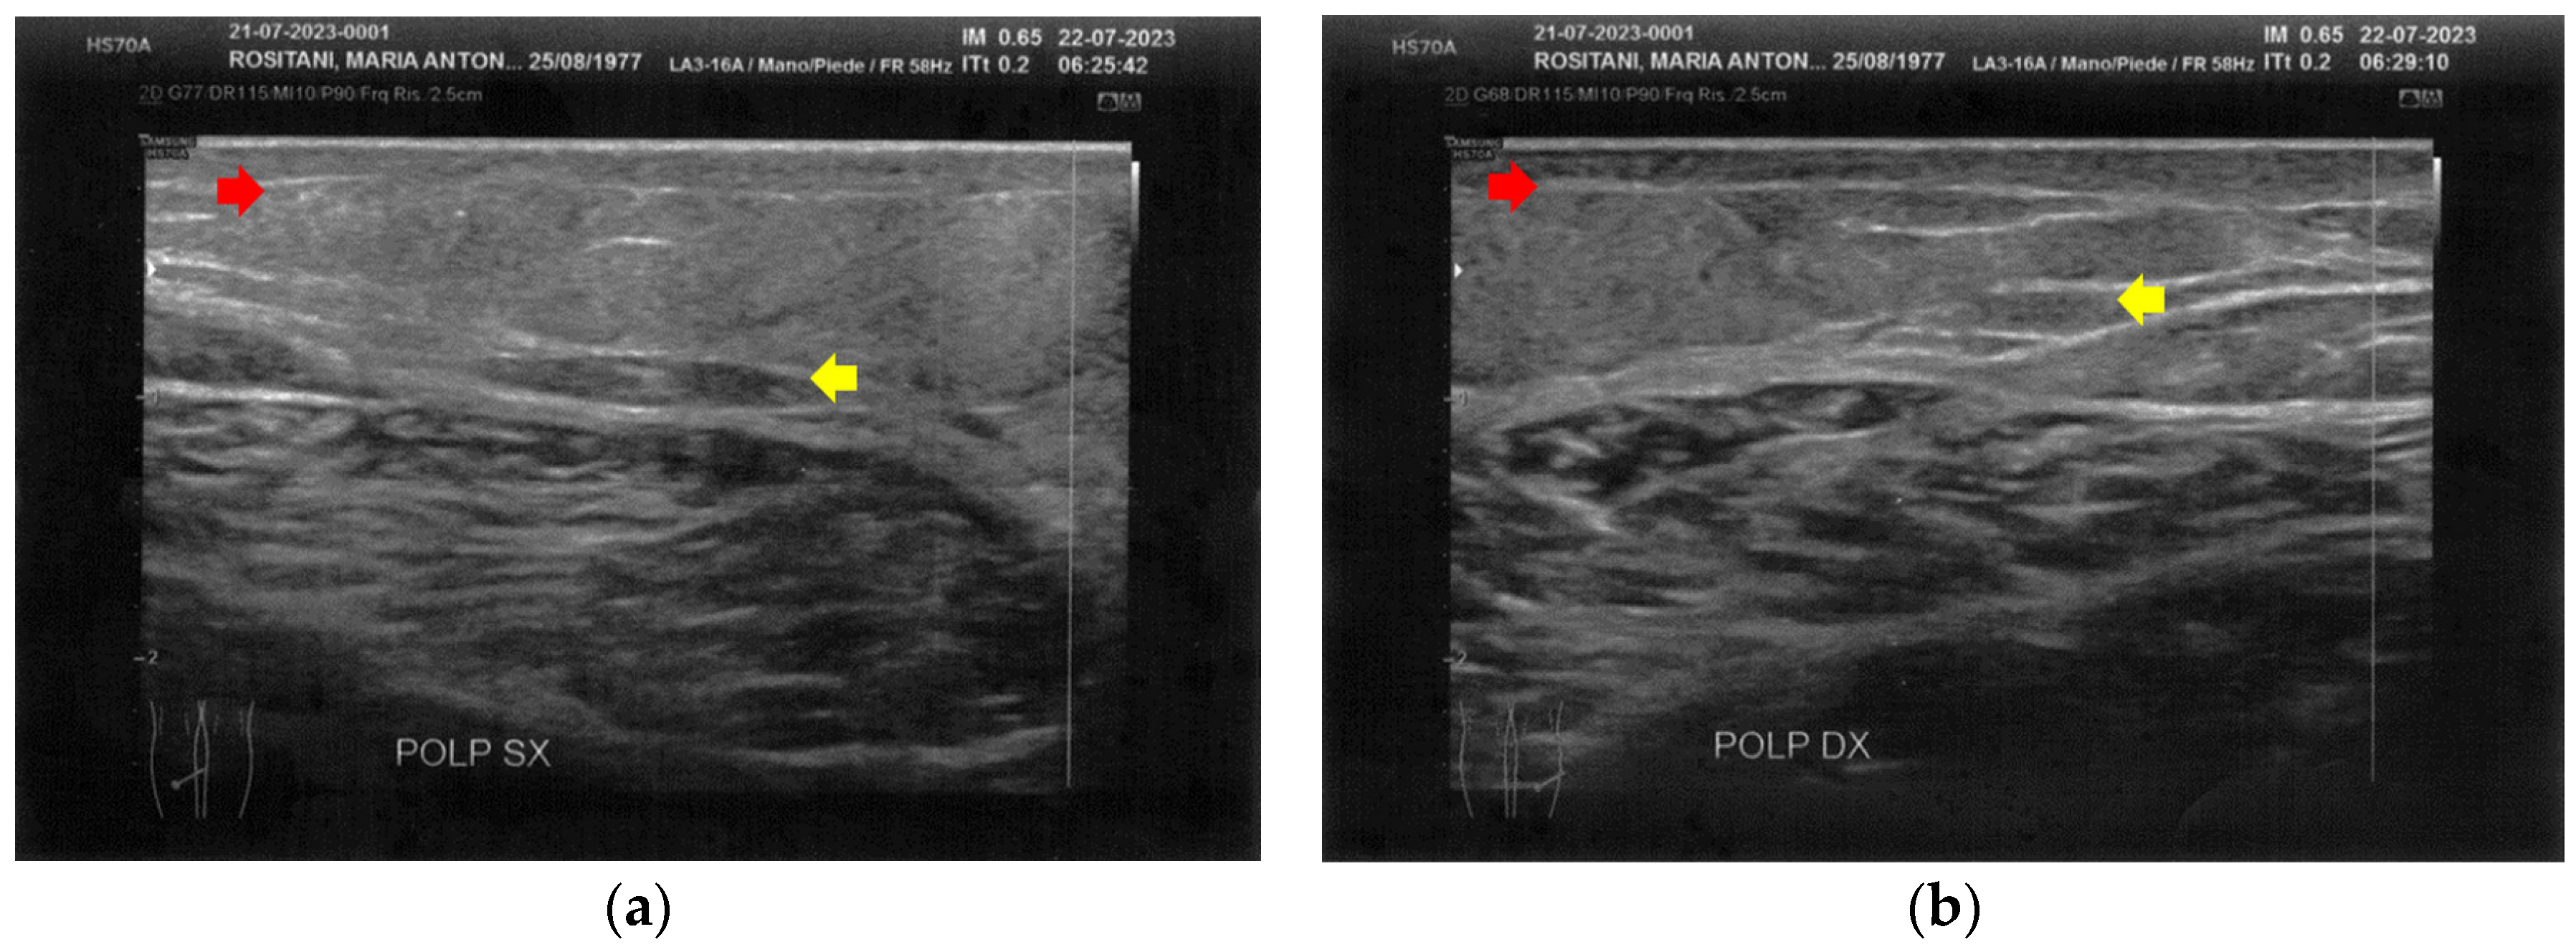

The left calf presented more severe alterations compared to the right calf. Both areas presented superficial cicatricial fibrosis. However, on the left side, a small fluid element of a probably phlogistic nature was observed at the muscular level, while on the right side, the muscular structure appeared intact (Figure 4).

Figure 4.

Ultrasonography of the calves at T0. (a) Cicatricial fibrosis (red arrows) is evident on the left calf on the superficial layers. Phlogosis extends to the deeper layers (yellow arrow). A small fluid element (white arrow) is observed at the muscular level; (b) Cicatricial fibrosis (red arrow) is also evident on the right side, where the muscular structure (yellow arrow) appears preserved.